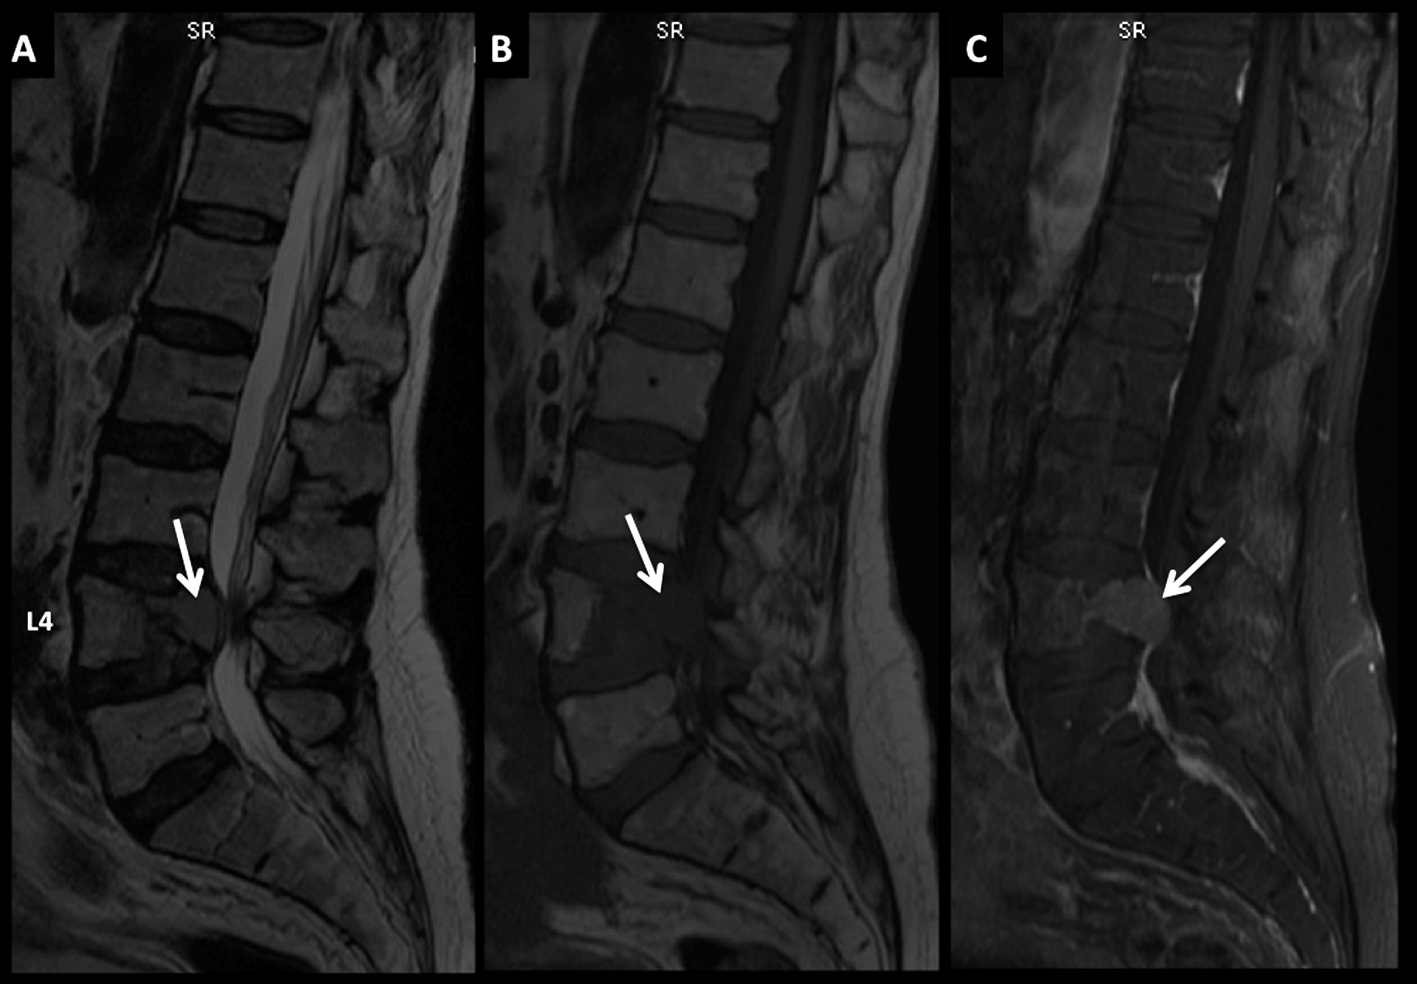

LNH, lesión ósea única, compromiso secundario. (cont)

Paciente con LNH y lesión ósea de sustitución en el cuerpo de L4 confirmada por punción, con aplastamiento y compromiso del canal raquídeo.

En RM, secuencia FSE T2 sagital (A) la lesión es heterogénea, predominantemente de alta señal. Es hipointensa en T1 (B) y tiene intenso realce con el medio de contraste (C).

Es claro el compromiso del muro posterior y la disminución de altura del cuerpo vertebral.

En el plano axial (T1 en D, T2 en E y T1 con contraste en F) se observa la proyección del componente lesional hacia el canal con compromiso severo del mismo (flecha discontínua).